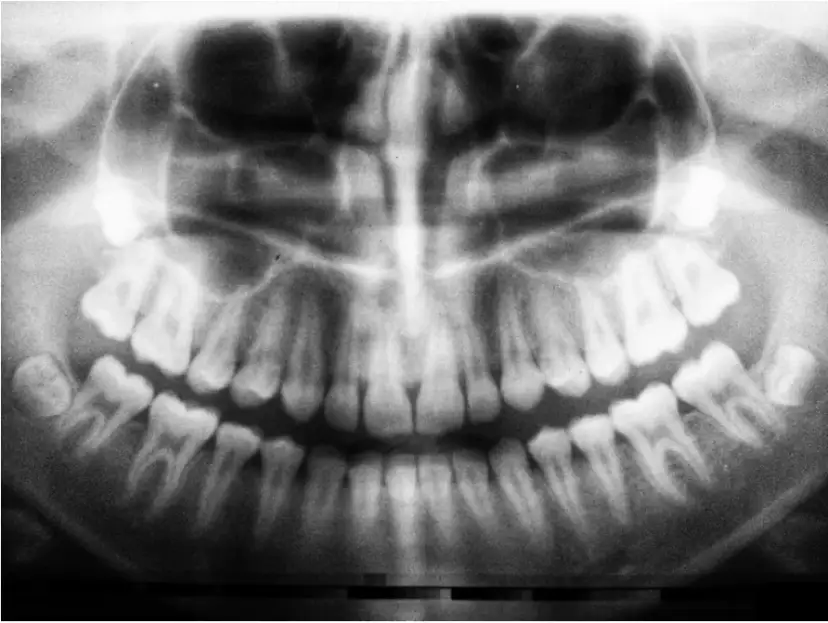

Na jakie zęby zakłada się aparat? Poznaj rodzaje aparatów ortodontycznych, proces leczenia wad zgryzu i dowiedz się, jak działa aparat na zęby przednie i tylne.